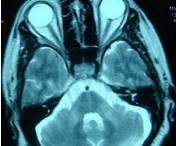

脊髓小腦性共濟失調

• 脊髓小腦性共濟失調

628健康網為您分享有關脊髓小腦性共濟失調的癥狀,脊髓小腦性共濟失調的治療方法,脊髓小腦性共濟失調的預防知識,脊髓小腦...

• 閉鎖綜合征

628健康網為您分享有關閉鎖綜合征的癥狀,閉鎖綜合征的治療方法,閉鎖綜合征的預防知識,閉鎖綜合征的癥狀圖片,閉鎖綜合征...